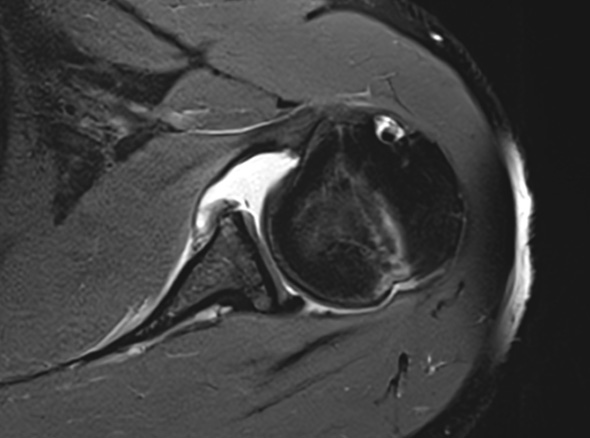

어깨가 가볍게 빠지는 증상, 어깨와 팔꿈치 사이에 있는

상완골이 어깨뼈에서 빠져나오는 증상을 어깨 탈구라고 합니다.

상완골두의 울타리 역할을 하는

관절와순 순상이 동반되는 경우도 있습니다.